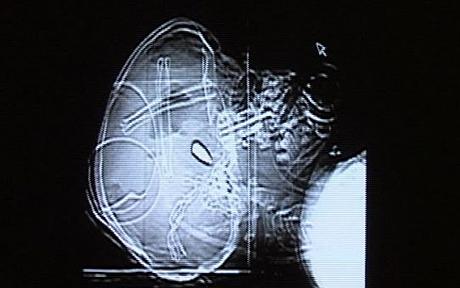

SHOT IN THE HEAD: GIFFORDS, HURNDALL AND PALESTINIAN CHILDREN

“I can’t precisely decide whether these children are being shot at as a target, but in some cases the bullet comes from the front of the head and goes towards the back, so I think the gun has been directly pointed at the child.”